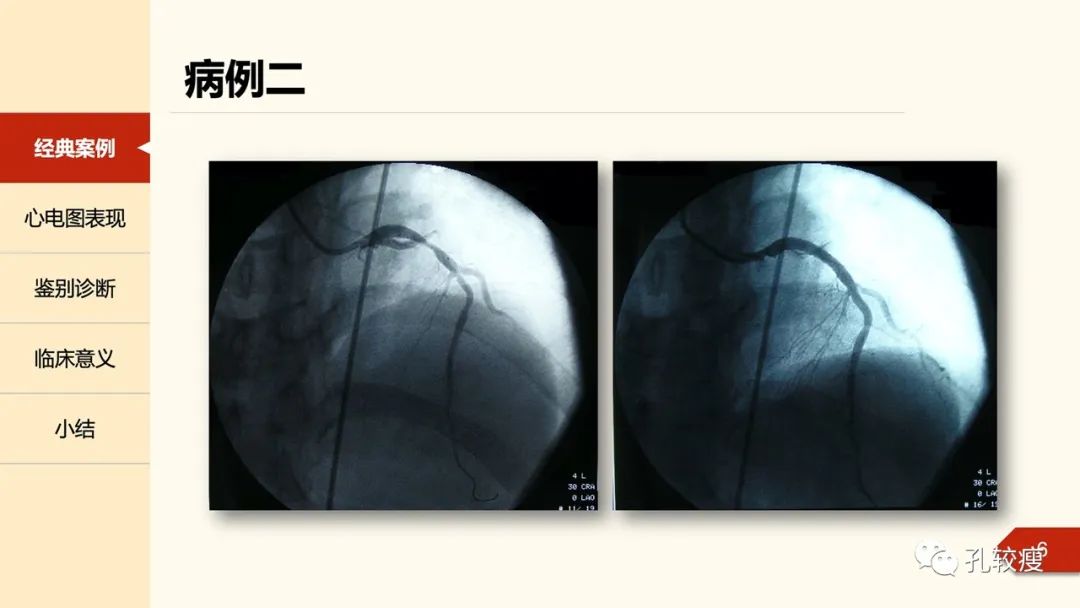

1979年, Gerson及其同事又描述36例运动后诱发的U波倒置的病案,实际上,这些表现类似于Wellens综合征的第二个亚型。当时人们以为双向T波的倒置部分为U波;这部分患者在冠脉检查中均提示存在前降支近端的狭窄。时隔一年,Gerson在文章中再次描述了部分患者在静息状态下仍可出现此类心电图改变,与心绞痛发作出现并不平行。

但Wellens所描述的这种心电图异常,更为广泛的引起了人们的重视而已。在1982年以后,Wellens团队在其后数年前多次撰文、详细总结、充分奠定了两种心电图异常在冠状动脉预警中的地位。于是,在上世纪90年代,心血管界开始广泛使用Wellens综合征这一名词。